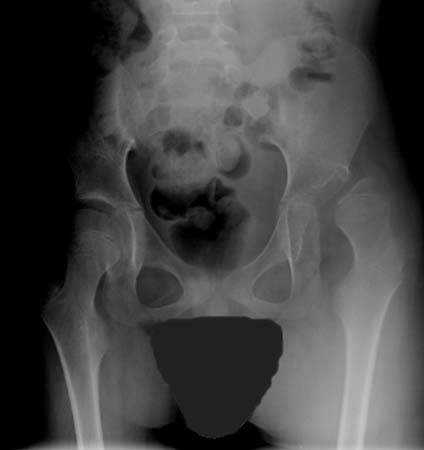

ცერებრული დამბლის მქონე პაციენტებში მენჯ-ბარძაყის სახსრის ამოვარდნილობა

William L. Oppenheim-ის კოლექციიდან; გამოყენება ნებადართულია